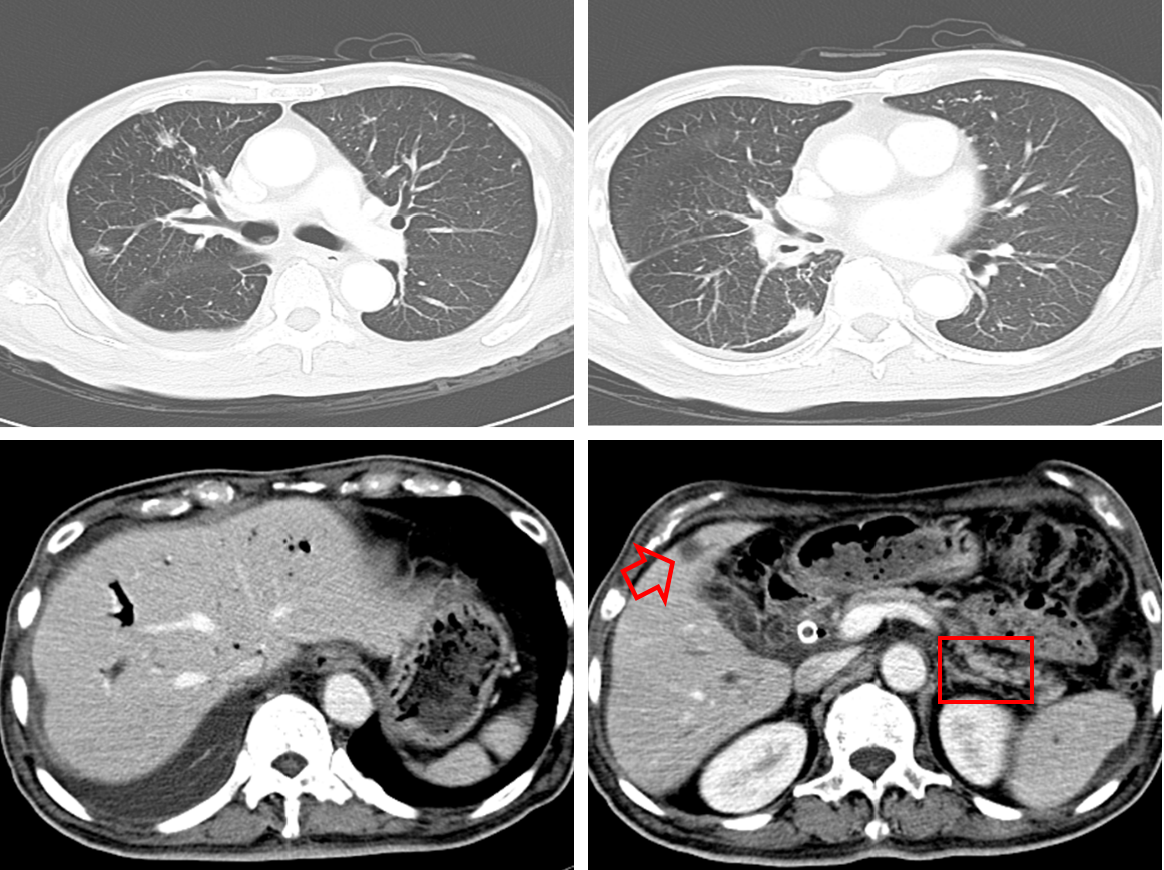

图4:系统治疗前胸部CT(左)和全身骨显像(右)

图5:免疫治疗前胸部CT

图6:免疫治疗前腹部CT

第二阶段:免疫联合治疗

经临床综合考量后,考虑予以患者免疫联合靶向药物治疗。患者经充分知情同意并签署知情同意书后,予以“安罗替尼 + 替雷利珠单抗”免疫联合治疗。

(1)免疫联合治疗2周期:

EOCG PS评分:1-2分。

实验室指标:总胆红素 23.2 umol/L,CEA 11 ug/L,ALB 33.5 g/L。

右肺靶病灶肿瘤直径:15×20 mm。

疗效评价:缩小的SD。

图7:免疫联合治疗2周期后胸部CT

(2)免疫联合治疗4周期:

实验室指标:总胆红素 20 umol/L,CEA 7.28 ug/L,ALB 33.5 g/L。

右肺靶病灶肿瘤直径:13×20 mm。

图8:免疫联合治疗4周期后胸部CT

患者为老年男性,确诊为“右肺腺癌,合并全身多处转移(T2N2M1c,IVB期,EGFR exon16 splicing,ALK缺失突变,KRAS 突变,TP53 突变,PD-L1:TPS<1%,TMB36.78/Mb,MSS)”。外院一线予以靶向药物吉非替尼治疗15天后疾病进展(PD),外院二线予以靶向药物埃克替尼治疗12天后再次PD。对患者进行充分的生物标志物筛查后,本院三线予以替雷利珠单抗联合安罗替尼治疗后,疗效评价为缩小的SD,EOCG PS评分从3~4分降至1~2分,意味着患者不仅获得了持久免疫应答,生活质量亦得到显著改善。治疗过程中不良反应轻微,安全性良好,患者可以耐受。